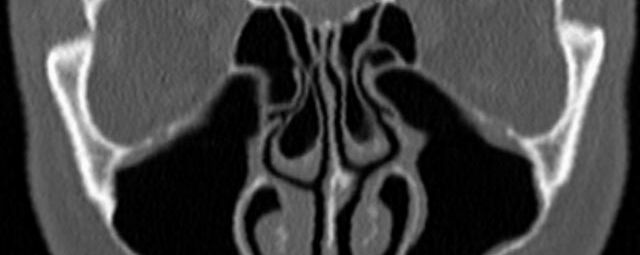

Kopf

• Nasennebenhöhlen (Entzündungen, Tumore)